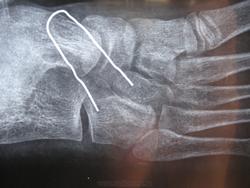

Появился небольшой бугорок на стопе. Сделали рентген. Выявлено "наличие персистирующего апофиза основания 5-й плюсневой кости".

8 месяцев назад небольшой бугорок был уже виден, но рентгенография стопы изменений не выявила.